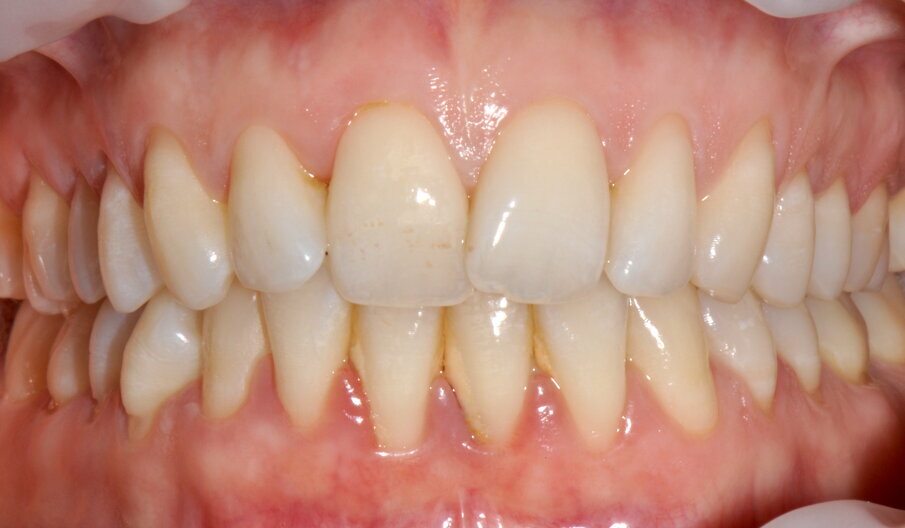

Si rivede la paziente a 2 settimane per valutare la guarigione (P. Mark Bartold, 2000) dei tessuti e la qualità del mantenimento domiciliare (Figg. 5a-5c).

Figg. 5a-5c - Rivalutazione a 2 settimane si noti la completa risoluzione dell’infiammazione gengivale, nelle visioni vestibolare (5a), palatale (5b) e linguale (5c).